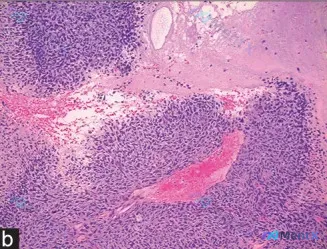

显微镜下见:

- 细胞密集呈实性巢状/片状,圆形/卵圆形/梭形,核浆比显著增高,核大小基本一致(单调性),染色质深染,核仁不明显;

- 间质稀少,但血管极丰富,可见扩张充血的血管穿插于细胞团间,伴区域性出血;

- 右上角可见大片肿瘤性坏死;

- 无明显慢性炎症细胞浸润背景。